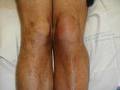

1. En la rodilla , la deformación más frecuente es la actitud en flexión. Quiste de Baker.